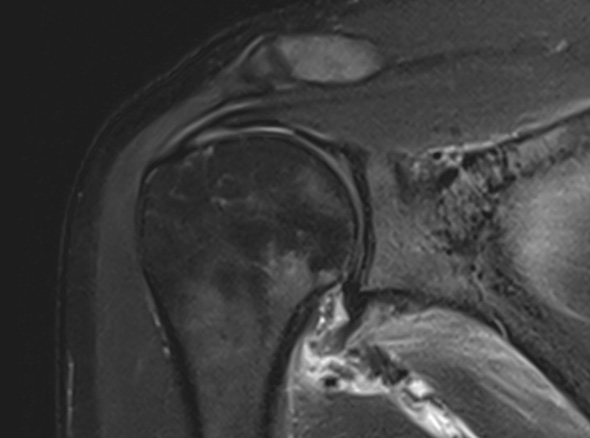

오십견은 어깨를 감싸고 있는 관절 조직인 관절낭에 염증이 발생하면서

유착되어 어깨의 움직임이 제한되고 통증이 유발되는 질환입니다.

오십견은 얼어버린 어깨라고들 부릅니다. 어깨가 움직이는 범위가 점점 줄어들면서

통증을 느끼는 질환입니다. 의학적인 용어로는 동결견, 유착성 관절낭염이라고도 합니다.